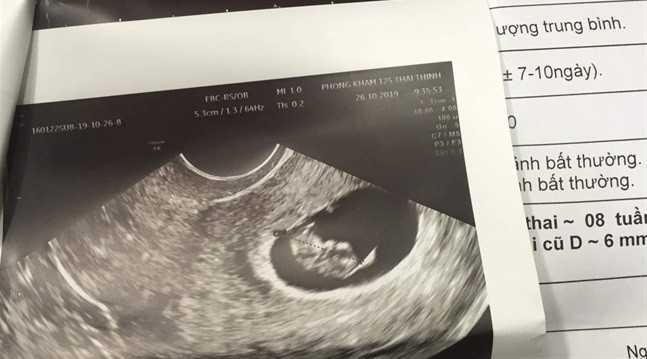

| Kết quả siêu âm cho thấy chị A. mang thai 8 tuần |

Khi về nhà, chị A bị mệt mỏi, khó thở, buồn nôn và các biểu hiện mỗi ngày một nặng hơn. Do sức khỏe không cải thiện, ngày 24/10, chị A đi khám tại một BV tư ở Hà Nội. Kết quả là chị A. đã có thai được 8 tuần. Như vậy, vào thời điểm hút mỡ bụng, chị A. đã mang thai hơn 4 tuần.

Ngày 28/10, cả hai Thẩm mỹ viện và chị A. đã đến một bệnh viện tư ở TP.HCM để kiểm tra. Bác sĩ cho biết, chị A có thai 8 tuần.